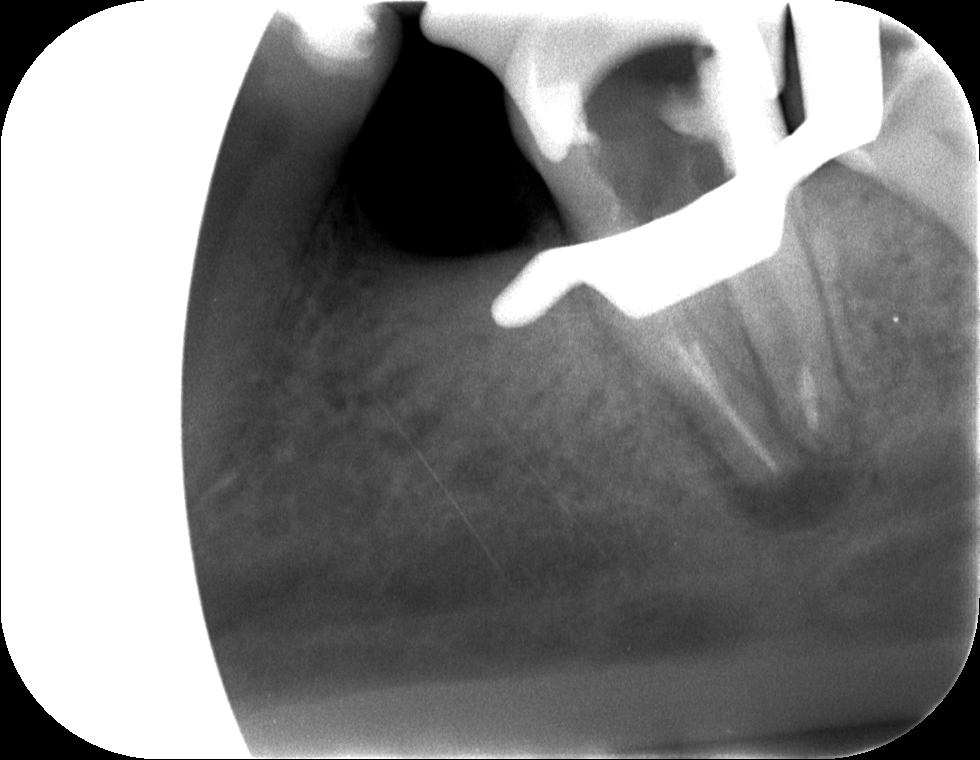

A kiindulási röntgenfelvételen jól látható, hogy a régi gyökértömés minősége nem a legmegfelelőbb, nem sikerült a gyökércsatornákat a teljes hosszon kitisztítani, ezáltal a fog gyökércsúcsa körül gyulladás alakult ki. (Az érintett területet pirossal rajzoltuk körbe.) Sajnos sokszor találkozunk ezzel a problémával. Ami talán még rosszabb, hogy ezek a gyulladások sokszor rejtve maradnak, egészen addig, amíg egyszer csak meg nem fájdul a fog. Ez történt most is, kedves páciensünk igen nagy fájdalmakkal érkezett.

Fog megmentése mikroszkópos kezeléssel kiindulási állapot